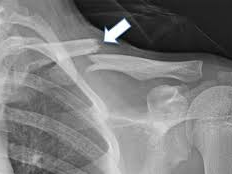

어깨에 골절이 발생하면 일상 전체가 마비되는 기분을 느끼는 것도 무리는 아닙니다. 특히 쇄골, 상완골 근위부, 견갑골 부위에 골절이 생기면 수술이 필요하며, 수술 이후의 재활과 물리치료는 단순히 통증을 없애는 것을 넘어, 관절 가동 범위의 회복과 장기적인 기능 정상화를 위한 핵심 단계입니다. 또한 어깨 골절 수술 이후 본격적으로 시작되는 재활 치료와 도수치료의 현실적인 문제는 ‘비용’과 ‘보험 적용 여부’입니다.